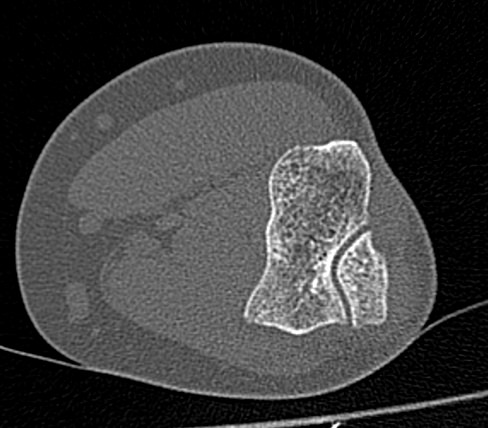

Одним из наиболее информативных методов исследования локтевого сустава является мультиспиральная компьютерная томография. Мультиспиральная КТ локтевого сустава позволяет оценить состояние костных структур и капсульно-связочного аппарата сустава. В отличие от обычного рентгена, при котором изображения накладываются друг на друга, мультиспиральная компьютерная томография с помощью рентгеновских лучей сканирует исследуемую область в разных плоскостях, делая множество тончайших срезов и преобразуя данные в цифровые трехмерные изображения.

Костная ткань хорошо поглощает рентгеновские лучи, поэтому кости ярко визуализируются на снимках КТ. Компьютерная томография в первую очередь востребована в ортопедии и травматологии. Методика широко применяется для диагностики костной патологии. С помощью КТ можно оценить плотность костной ткани и выявить косвенные признаки остеопороза. В случае перелома можно определить точную локализацию костных отломков, что особенно важно при планировании оперативного вмешательства и в послеоперационном периоде для наблюдения за процессом восстановления. КТ также помогает в диагностике различных артритов и артрозов.

- Что покажет КТ локтевого сустава

Что покажет КТ локтевого сустава

- врожденные особенности строения;

- сокращение плотности костей при остеопорозе;

- воспалительные процессы не только в самом суставе, но и в тканях, которые окружают его;

- переломы и трещины костей;

- дегенеративно-дистрофические изменения;

- гнойные процессы;

- инородные тела

- новообразования костей и мягких тканей (не только первичные опухоли, но и метастазы).